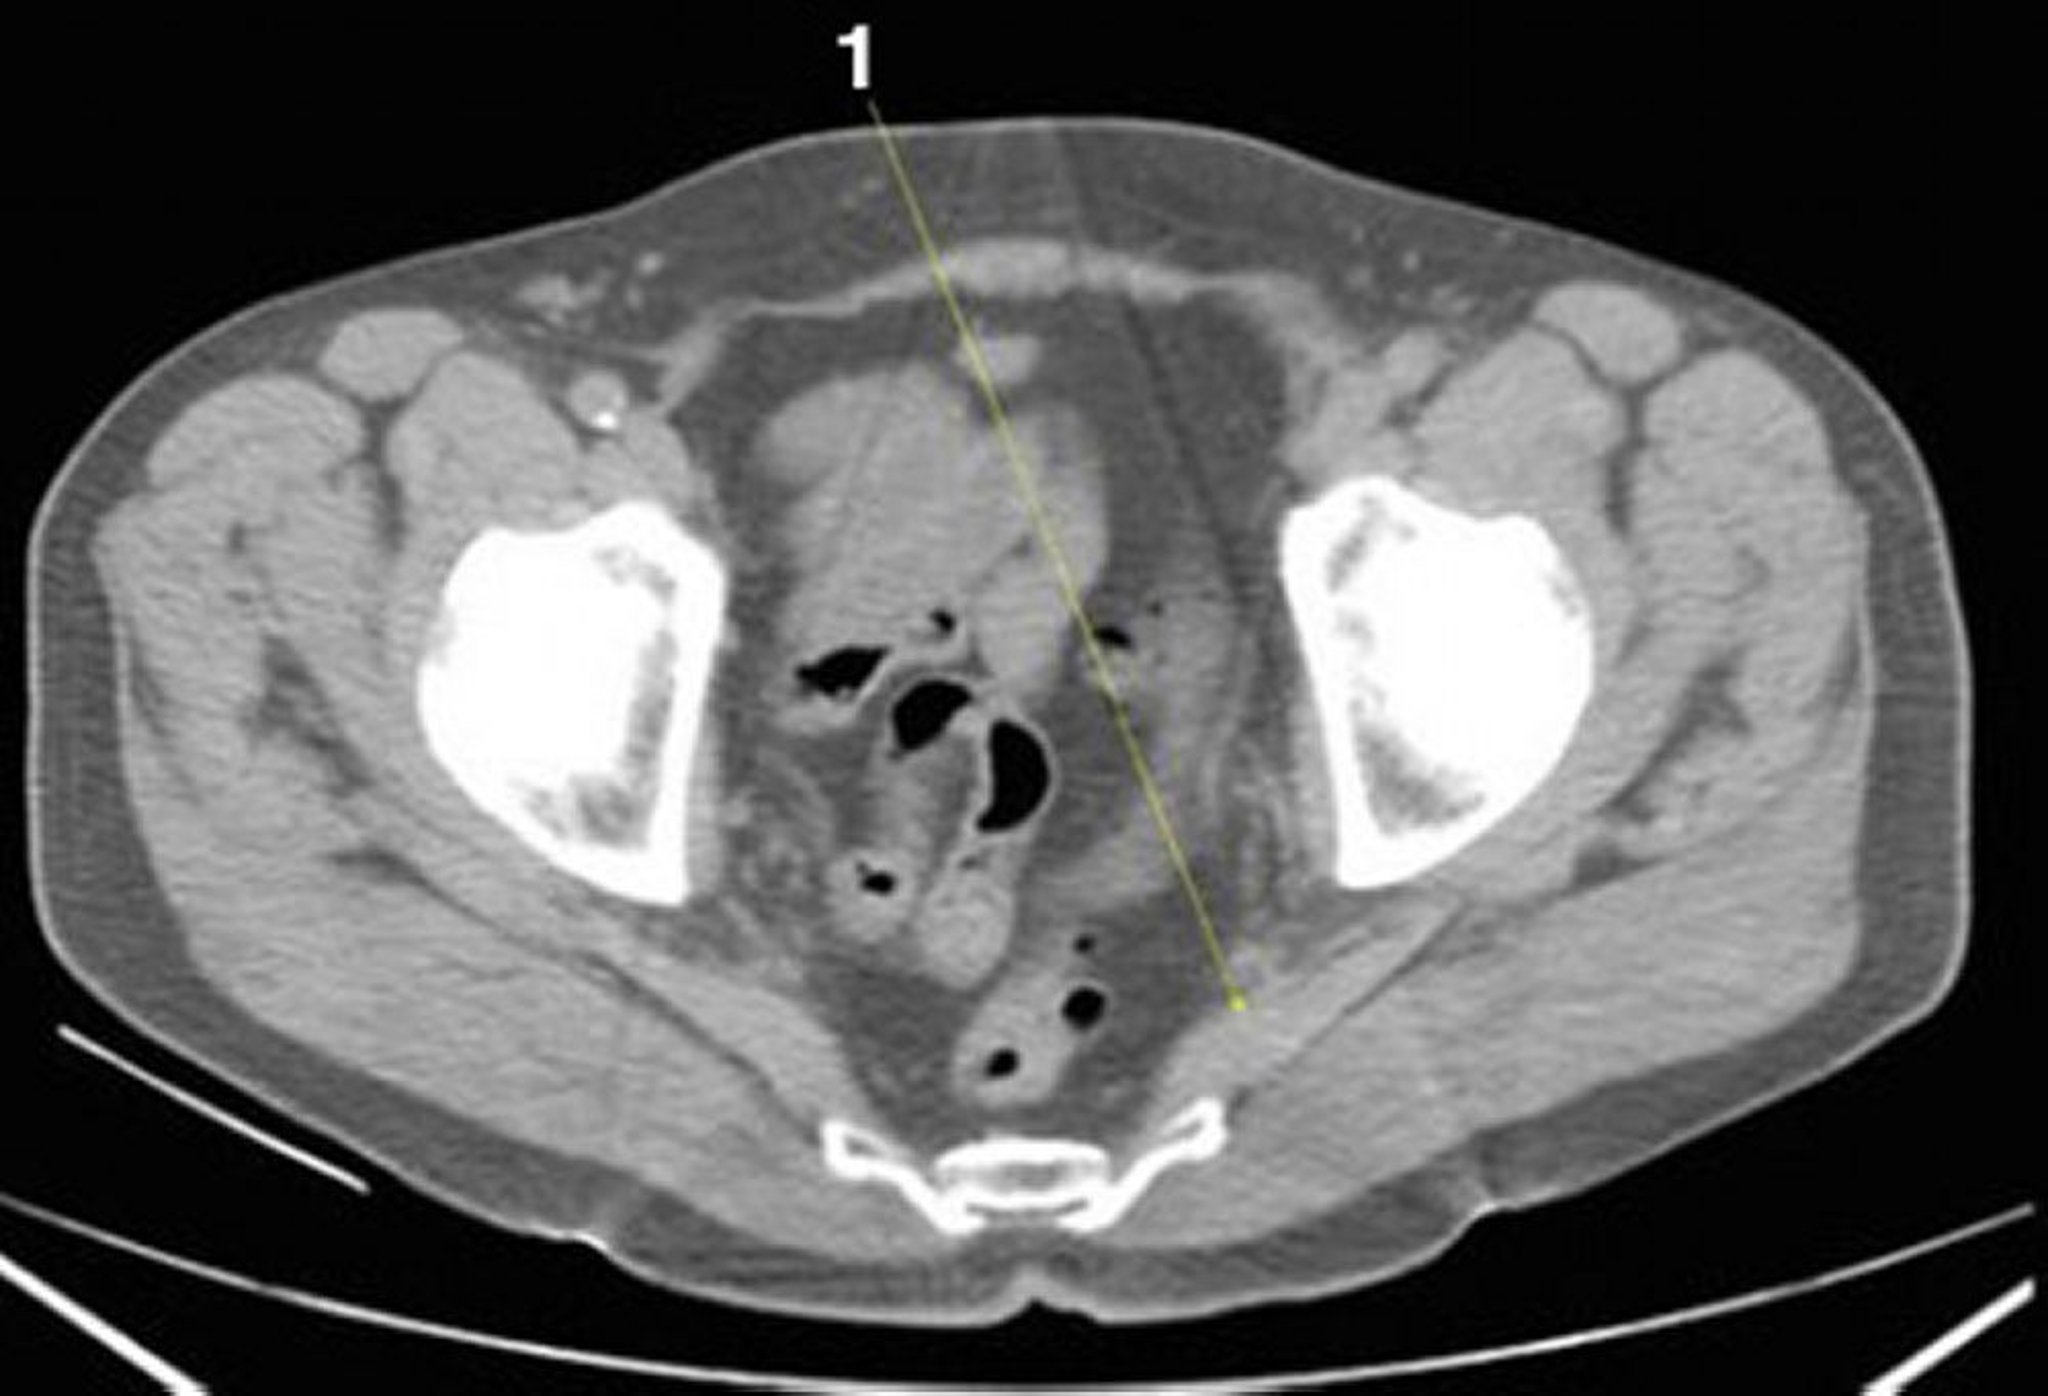

CT-Scan von Abdomen und Becken mit normaler Anatomie ohne Kontrastmittel (Folie 26)

1 = M. piriformis.